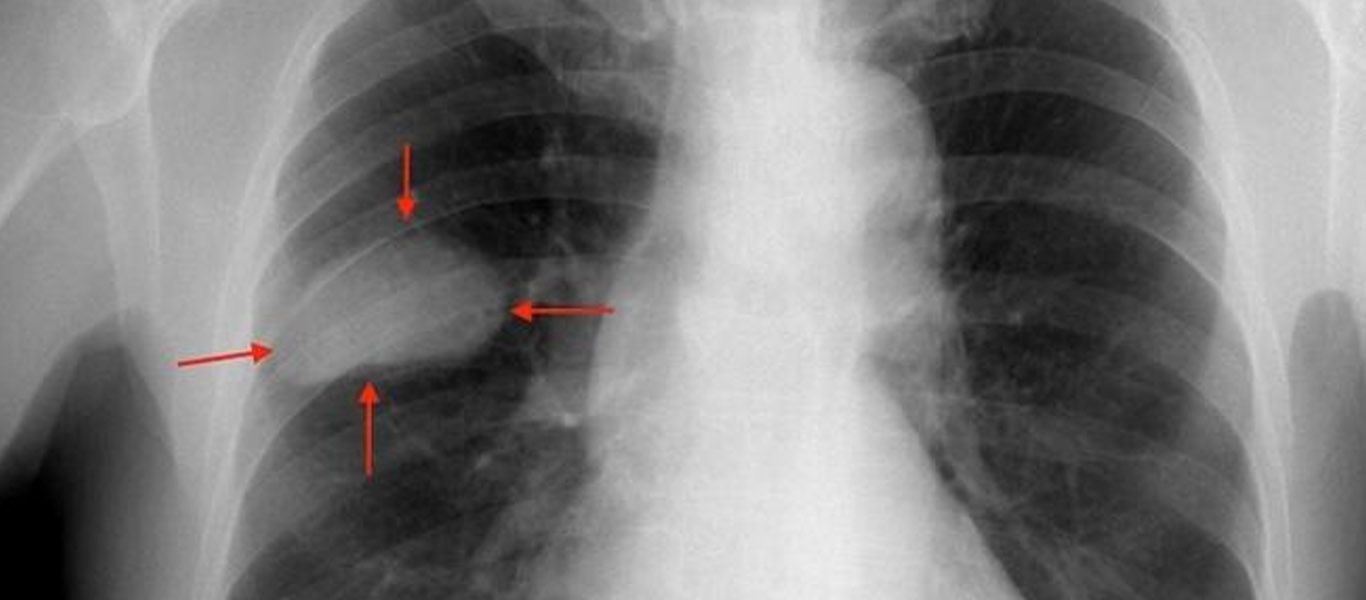

¿Cómo se diagnostica el cáncer de pulmón?

Nuestro equipo trabaja de forma conjunta con los servicios de Oncología, Diagnóstico por Imágenes, Radioterapia y Patología, logrando brindar un abordaje multidisciplinario que nos permite ofrecer el mejor diagnóstico y tratamiento disponible para el cáncer de pulmón en todos sus estadios. Al enfrentar un cáncer de pulmón lo más importante es realizar un diagnóstico de certeza y suficiente para poder decidir cómo será tratado, para lo cual hay que procurar tomar biopsias de buena calidad o resecar completamente el tumor.